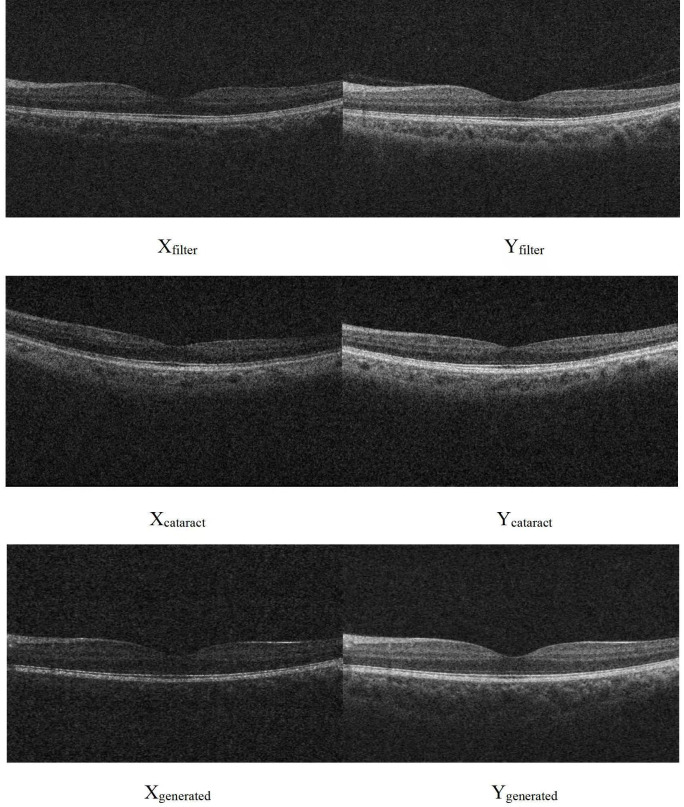

Methods: In this cross-sectional study, a spectral-domain OCT (Zeiss Cirrus 5000, Germany) was used to scan the macula of 510 eyes from 272 Chinese subjects. Optical media opacity was simulated with an algorithm for training set (420 normal eyes). Images for three test sets were from the following: 56 normal eyes before and after fitting neutral density filter (NDF), 34 eyes before and after cataract surgeries and 90 eyes processed by algorithm. GANs of pix2pix was trained with training set and restored blurred images in test sets. Structural similarity index (SSIM) and peak signal-to-noise ratio (PSNR) were used to evaluate the performance of GANs.

Results: PSNR for test sets before and after image restoration was 18.37±0.44 and 19.94±0.29 for NDF (p<0.01), 16.65±0.99 and 16.91±0.26 for cataract (p=0.68) and 18.33±0.55 and 20.83±0.41 for algorithm regenerated graph (p<0.01), respectively. SSIM for test sets before and after image restoration was 0.85±0.02 and 1.00±0.00 for NDF (p<0.01), 0.92±0.07 and 0.97±0.02 for cataract (p<0.01) and 0.86±0.02 and 0.99±0.01 for algorithm regenerated graph (p<0.01), respectively.

Conclusions: GANs can be used to restore blurred OCT images caused by optical media opacity in eyes. Future studies are warranted to optimise this technique before the application in clinical practice.